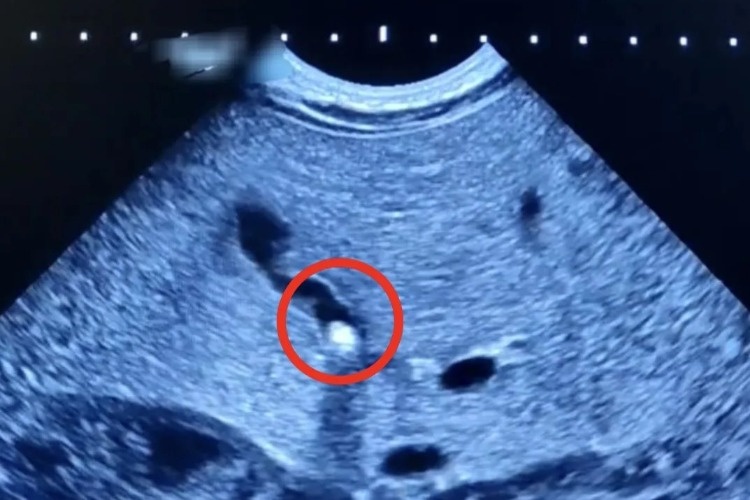

Врачи Балаковской городской клинической больницы отмечают опасную тенденцию: холецистит (воспаление желчного пузыря) и холелитиаз (наличие камней в желчном пузыре) стремительно «молодеют». В декабре текущего года эта патология, характерная для взрослых, была диагностирована у полуторамесячного младенца. При проведении УЗИ брюшной полости у него был обнаружен камушек в желчном пузыре. - За 30 лет практики это лишь второй подобный случай на моей памяти. Раньше желчнокаменная болезнь считалась заболеванием пожилых людей, но теперь данная патология встречается и у подростков, и даже у новорожденных, - рассказала заместитель главного врача по оказанию медицинской помощи детям Алла Николаевна Кудрявцева. Ребенок поступил в стационар с жалобами мамы на плохую прибавку массы тела и желтушное окрашивание кожи и склер у новорожденного. При обследовании выяснилось, что желчный проток частично закрыт камнем небольших размеров. Находясь в стационаре, малыш получал всё необходимое лечение. Врачам удалось не только улучшить отток желчи из желчного пузыря, но и добиться стабильной прибавки в весе, которой не наблюдалось в первый месяц жизни ребенка. Сейчас пациент выписан домой и находится на амбулаторном наблюдении. - Одна из причин данной патологии может скрываться в погрешностях в питании мамы на разных сроках беременности. Беременным и кормящим женщинам необходимо максимально ответственно подходить к данному вопросу, всегда тщательно следить за рационом, - подчеркнула Алла Николаевна.